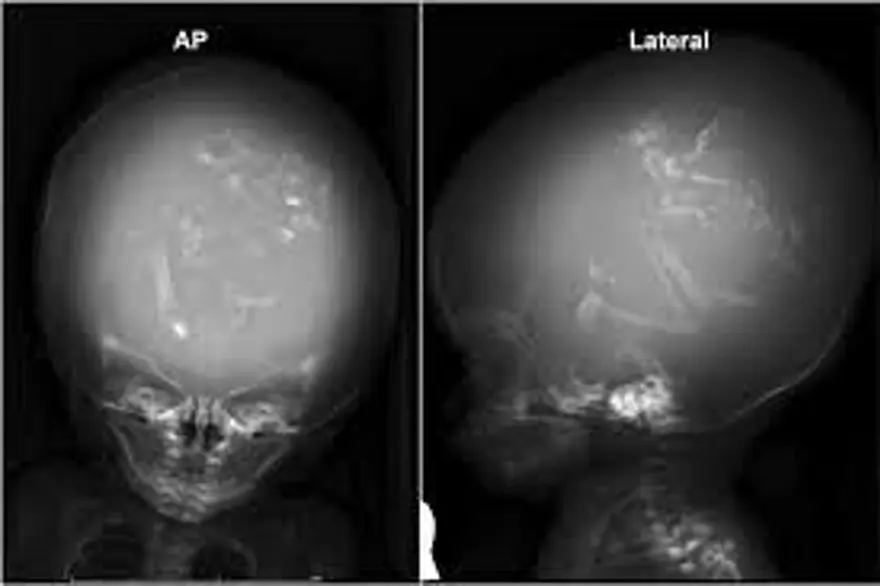

Çin'de doğmamış ikizinin fetüsü, bir yaşındaki kız bebeğin kafatasından ameliyatla çıkarıldı. 'Fetüs içinde fetüs' adı verilen oldukça nadir vakada, doktorlar fetüsün üst uzuvlarının, kemiklerinin ve hatta tırnaklarının gelişmiş olduğunu, yani kardeşinin içindeyken aylarca büyümeye devam ettiğini söyledi.Yaklaşık beş santim uzunluğundaki fetüs, ancak ebeveynler kızlarını kafası büyüdüğü ve motor becerilerinde sorunlar yaşadığı zaman doktora götürdüklerinde fark edildi.

Neurology dergisinde yayınlanan çalışmada, çocuğun motor fonksiyonlarında sorunlar yaşaması ve kafasının büyümesi üzerine ebeveynleri tarafından hastaneye getirildiği ortaya çıktı.

Şangay'daki doktorlar, doğmamış ikizin fetüsünün çocuğun beyninde geliştiğini tespit etti. Çalışmanın yazarları, "Motor becerilerinde gecikmesi ve genişlemiş baş çevresi olan 1 yaşındaki bir kız çocuğunda malforme olmuş monokoryonik diamniyotik ikiz olan intraventriküler fetüs içinde fetüs (fetus-in-fetu) tespit edildi." denildi.